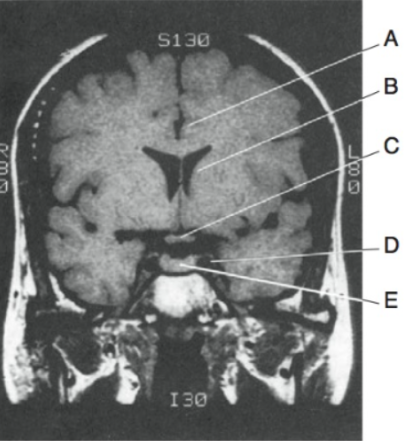

location of basal nuclei/ganglia? function?

neuronal cell body masses beneath cerebral cortex in each hemisphere

motor control + other

caudate nucleus → C shape, frontal to temporal

lenticular nucleus → putamen + globus pallidus, lat. + partial ant. to thalamus

what is the internal capsule of the basal nuclei/ganglia?

white matter, thick fiber sheet separating lenticular nucleus from thalamus + caudate nucleus

contains fibers interconnecting cerebral cortex, thalamus, caudate nucleus